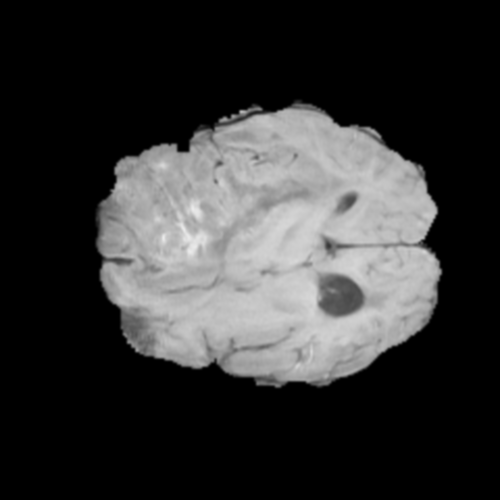

Ejemplos de Modalidades MRI

Visualización de las 4 modalidades de resonancia magnética y las segmentaciones de zonas tumorales utilizadas para entrenar el modelo

Glioma de Alto Grado (HGG)

FLAIR HGG

FLAIR

T1ce HGG

T1ce

T2 HGG

T2

T1 HGG

T1

📊 Modalidades de MRI Utilizadas

• T1: Secuencia ponderada en T1, proporciona gran detalle anatómico con líquidos oscuros

• T1ce: T1 con realce de contraste (Gadolinio), ilumina partes activas del tumor con barrera hematoencefálica comprometida

• T2: Secuencia ponderada en T2, sensible a patologías donde líquidos aparecen brillantes

• FLAIR: Recuperación de inversión atenuada en fluidos, similar a T2 pero suprime señal de LCR para visualizar edema peritumoral